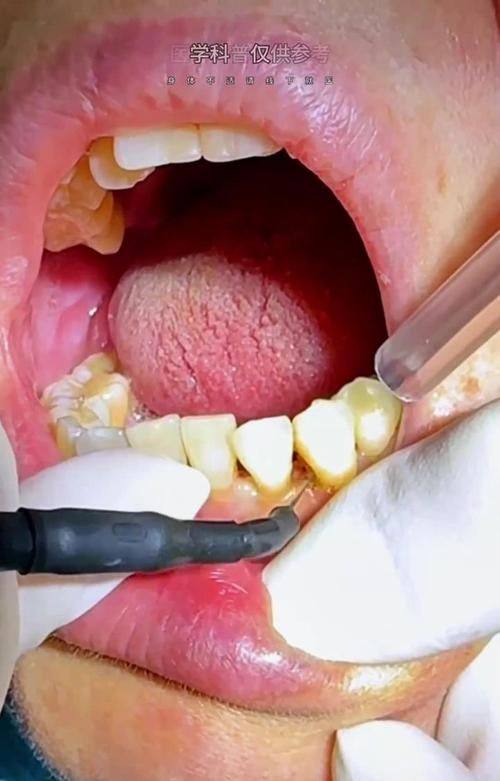

口腔保健:包含超声波洗牙、口腔检查等保健项目,帮助患者维护口腔健康,在线预约可享受检查费0元的补贴。